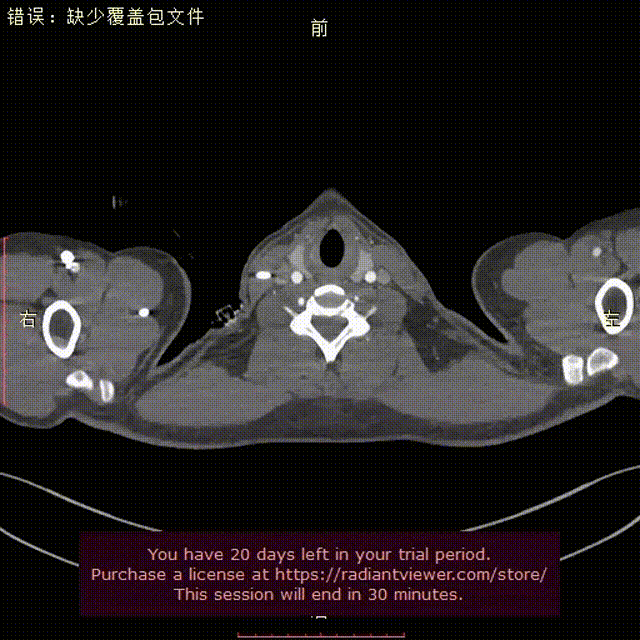

术前CTA提示右弓右降、合并Kommerell憩室,弓上各分支镜像分布。测量如下:

右弓右降,弓型陡峭,角度在40°左右

Kommerell憩室,38mm*30mm